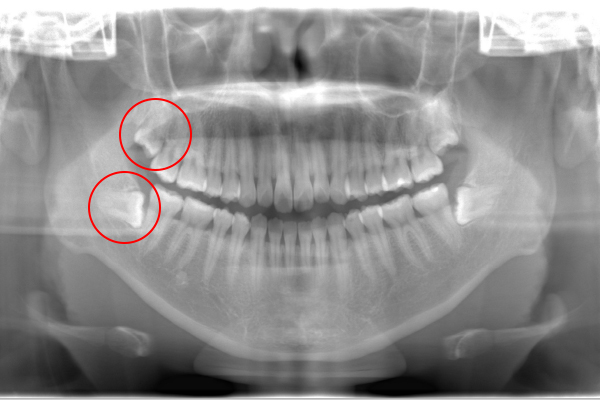

Case.02

親知らず抜歯Case.01 親知らず抜歯Case.01

患者様の要望親知らずを2本同時に抜歯したい

治療期間約60分

治療費用約10,000円(保険診療、CT撮影代込み)

治療内容水平に埋まっている智歯の抜歯

治療のリスク術後、腫れや痛みが出る可能性があり